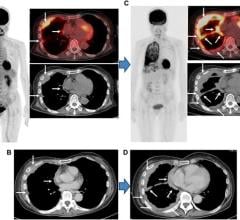

Amazon.co.jp: Learning Cardiac CT: A Board Review : Sharim, Medtronic launches new MRI cardiac therapy defibrillators,

Medtronic launches new MRI cardiac therapy defibrillators, New 256-Slice CT Scans Heart in Two Beats | Imaging,